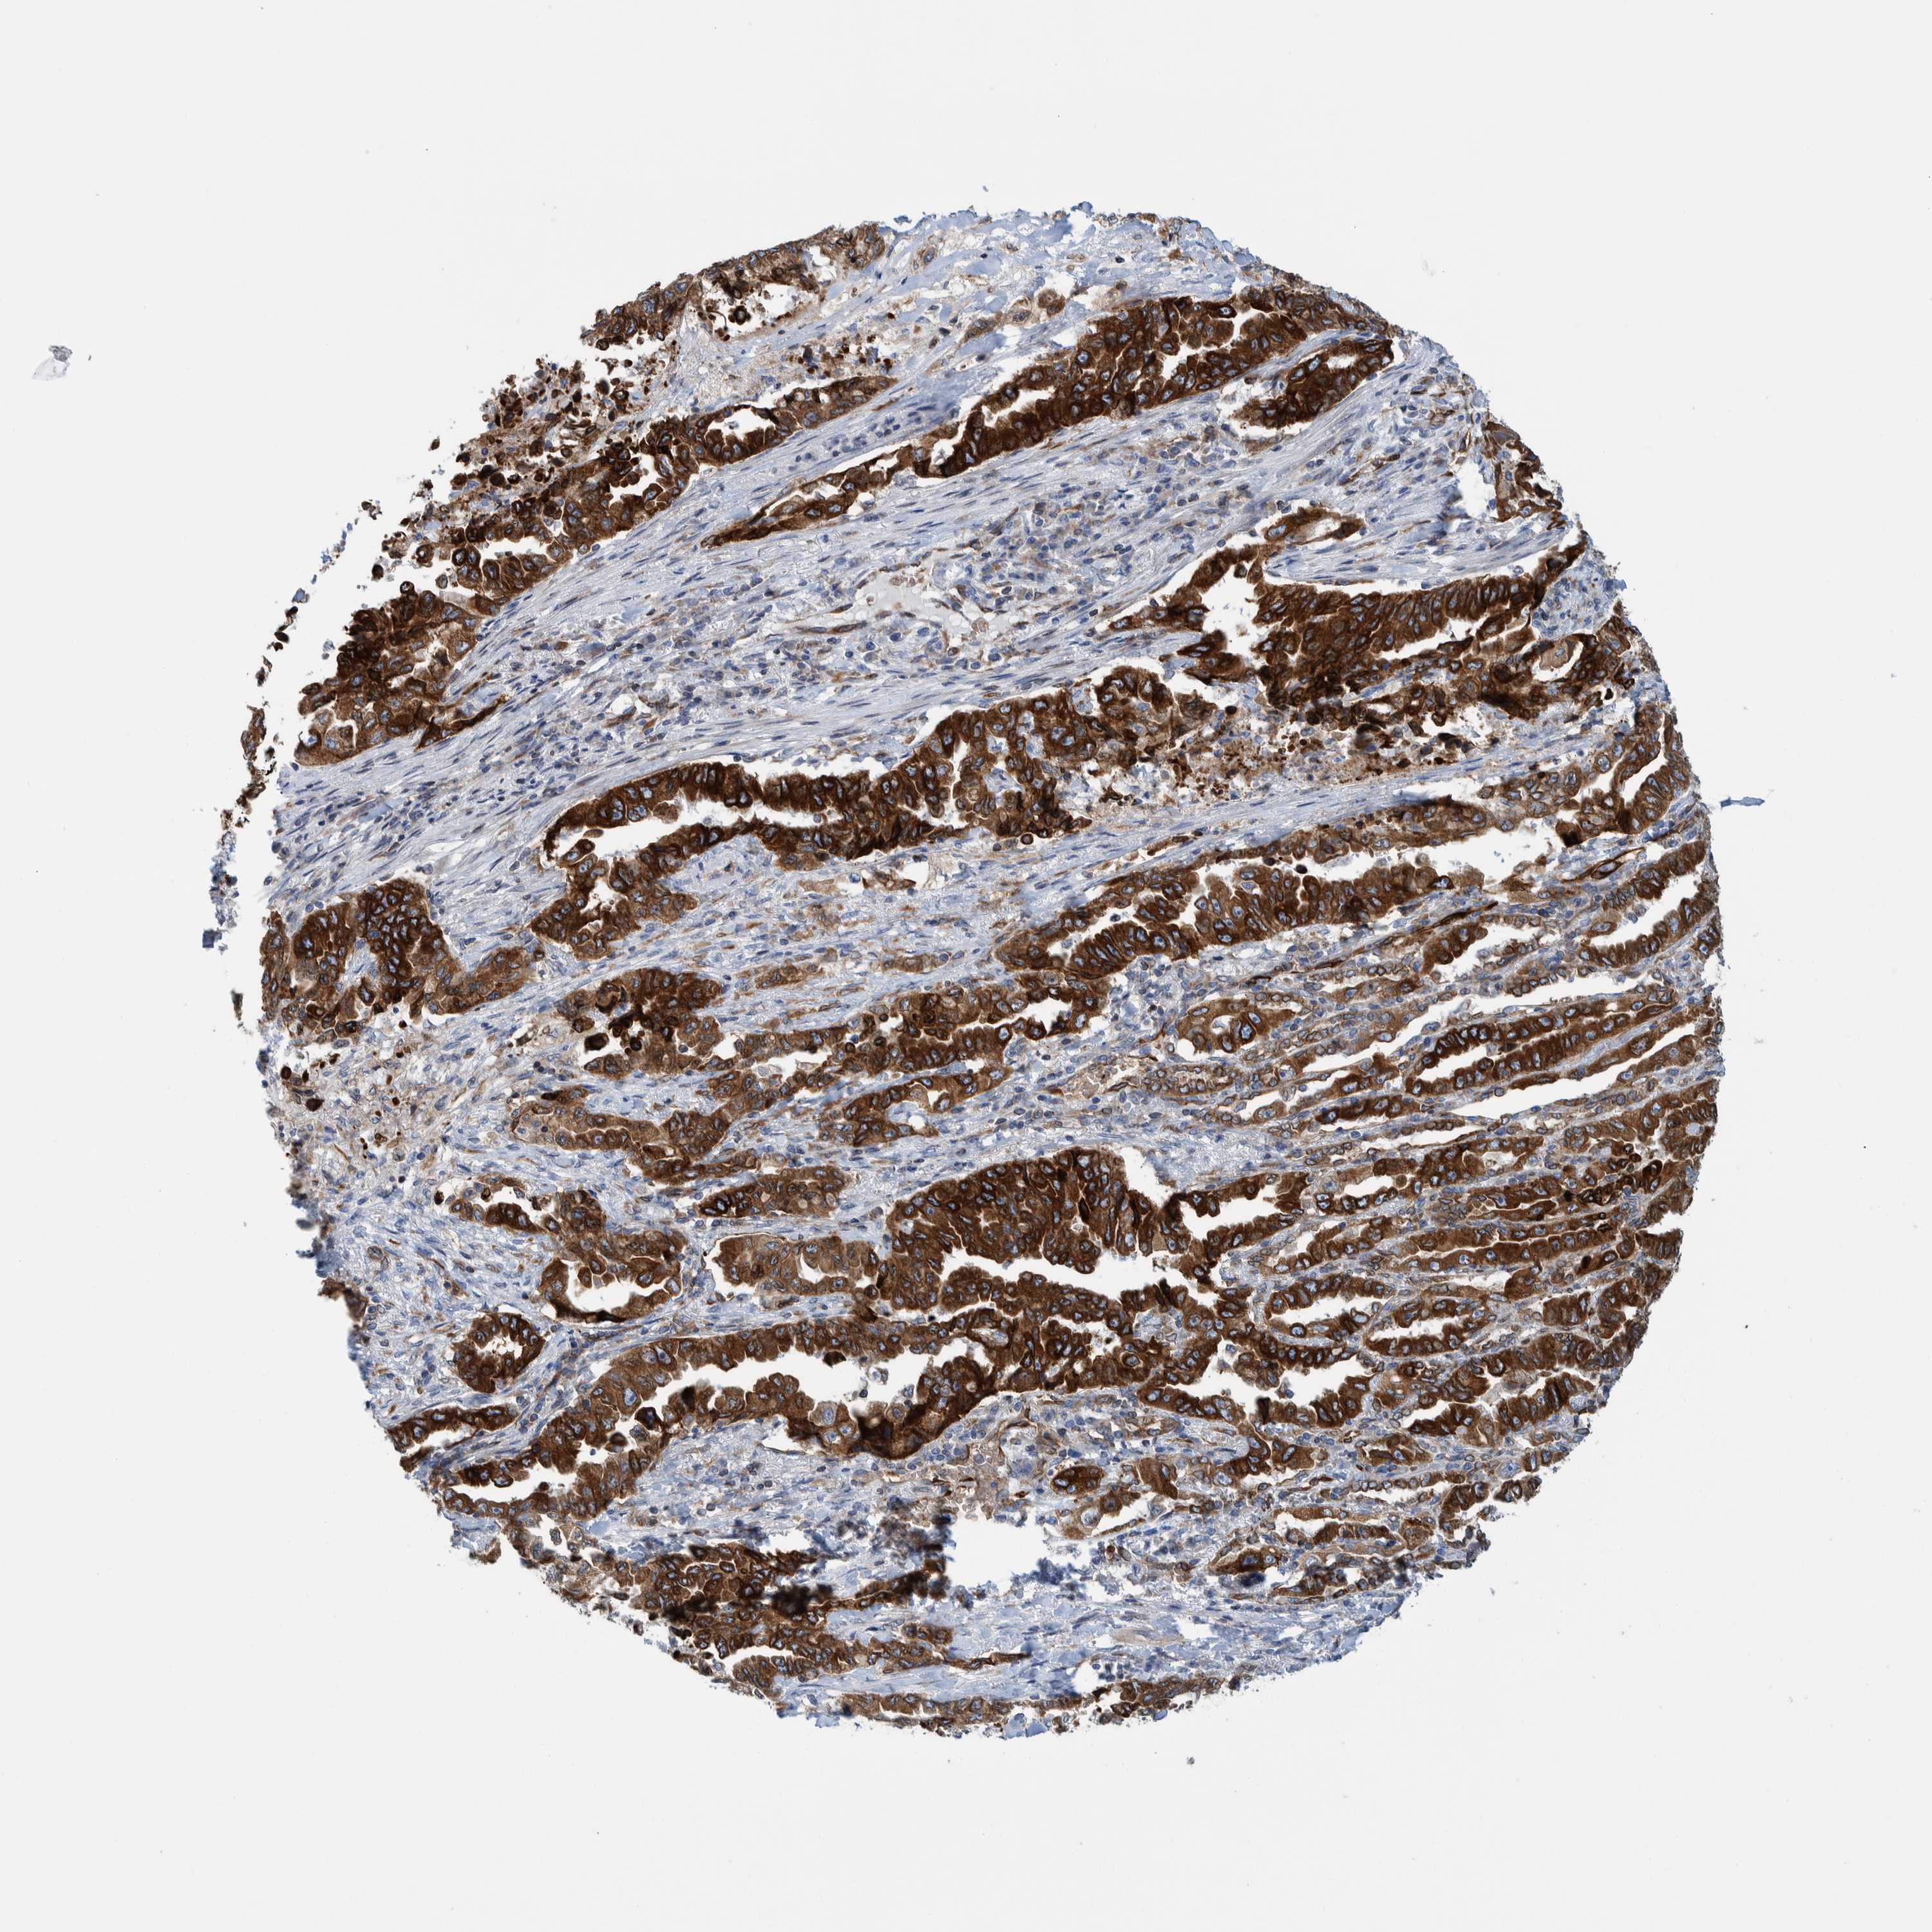

CANCER LUNG CANCER Show tissue menu

Lung cancer

Human cancer

Lung adenocarcinoma

Lung squamous cell carcinoma